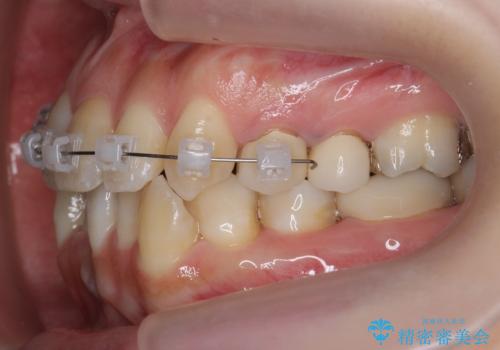

右上2番をしっかり並べるにはワイヤー矯正を上顎部分的に用いて、最後全体マウスピース治療を行いました。

上顎前歯は神経がない歯で色も変わってきていたためセラミックでかぶせています。